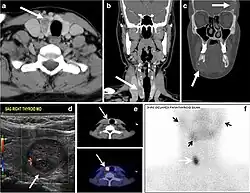

Thyroid scanning with technetium-99 m (Tc99m) plays an important role in detecting orthotopic and ectopic thyroid tissue. Both CT scans and US can help detect ectopic tissue when a lesion demonstrates imaging and enhancement characteristics of thyroid tissue. The absence of normally sited thyroid gland in US and CT scans also supports the diagnosis. In addition, US can guide FNA for cytological confirmation of a thyroid lesion. Ectopic thyroid tissue appears as a well-circumscribed, homogeneous, highly attenuating mass relative to adjacent muscles. Normally, it enhances avidly following the administration of iodinated contrast.[1]

Parathyroid adenoma (PA) is the most common cause of primary hyperparathyroidism. Ectopic parathyroid adenoma is rare. The third and fourth pharyngeal pouches represent the embryological origin of the parathyroid tissues, and ectopic parathyroid adenoma can ultimately develop anywhere along their migration course. In a large retrospective study of patients with primary hyperparathyroidism, PA was detected in the intra-thyroid location in 0.7% of cases. In another retrospective analysis of 202 patients with ectopic PA, the intra-thyroidal location was found in 18% of the cases. Intra-thyroid parathyroid adenomas mimic thyroid nodules in CT scans and may even show uptake on a thyroid iodine scan. Correlation with laboratory workup, including measurement of serum parathyroid hormone and calcium level, is required. In addition, the evaluating radiologist should search for radiological manifestations of hyperparathyroidism, such as osteopenia, bone resorption, and brown tumours (Fig. 22).[1]

In the case of inconclusive Tc99m Sestamibi and neck US imaging, FNA biopsy with FNA-iPTH (intact parathyroid hormone) measurement can provide simultaneous biochemical and cytological evidence. Elevated FNA-iPTH measurement, as compared to serum iPTH, is considered positive and diagnostic of parathyroid adenoma.[1]